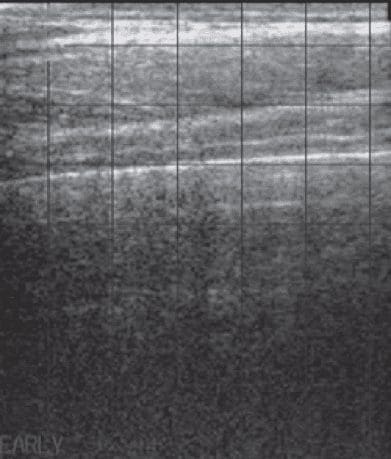

The presence of air within the normal lung prevents the ultrasound waves from penetrating deeply into the lung parenchyma. Therefore, the highly reflective pleural surface which is in contact with aerated lung. Is readily identified on ultrasound as a uniformly hyperechoic line which moves in synch with respiration. Figure 3 shows the surface of the lung in a normal cow with no evidence of pulmonary disease.

3 – Normal ultrasound appearance of the bovine thorax